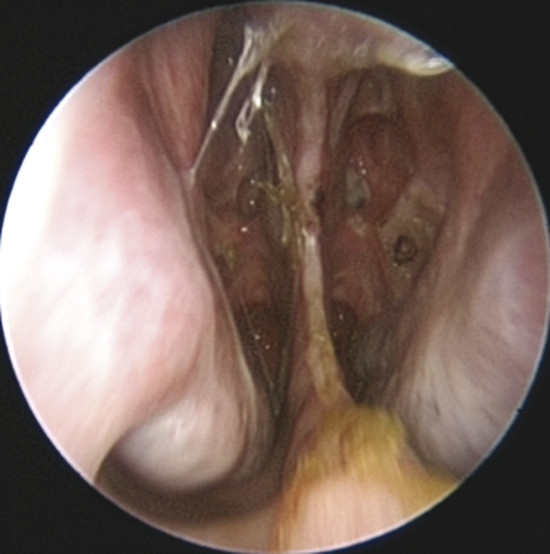

Upon physical examination of the nose, a full diagnosis cannot be made until all crusts have been removed and decongestion of the turbinates has taken place, making it possible to visualize the entire nasal septum. The nasal endoscopy allows appreciating the configuration of the NSP, the presence or absence of adherent crusts on the edges of the defect (Fig. 6‑1), any easily bleeding areas (Fig. 6‑2), and the state of the remaining mucosa, which may present some aspects regarding ischemic conditions (cocaine abuse) (Fig. 6‑3).